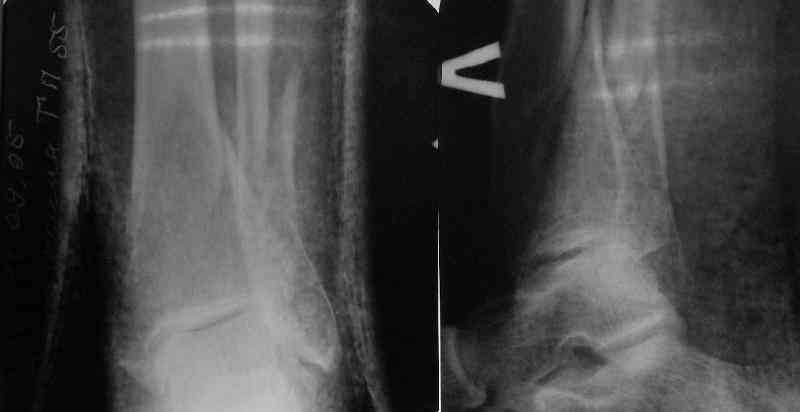

In delayed cases acute length restoration performed only in the tibia may leave the fibula shortened thus change the mortise. So it is reasonable to restore length of both bones simultaneously by distractor and fix the fibula not with open reduction and plating but just by a single perQ screw. Example attached.

[ Ответить ]